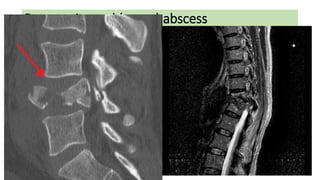

Retroperitoneal (psoas) abscess

• At the start of the twentieth century, psoas abscess was mainly

caused by TB of the spine (Pott’s disease).

• With the decline of M. tuberculosis as a major pathogen in resource-

rich countries,

• a psoas abscess was mostly found secondary to direct spread of

infection from the inflamed ± perforated digestive or urinary tract.

• In recent years a primary psoas abscess due to haematogenous

spread from an occult source is more common, especially in

immunocompromised and older patients, as well as in association

with intravenous drug misuse.

Clinical presentation

• Back pain, lassitude and fever.

• A swelling may point to the groin as it tracks along iliopsoas.

• Pain may be elicited by passive extension of the hip

• or a fixed flexion of the hip evident on inspection.